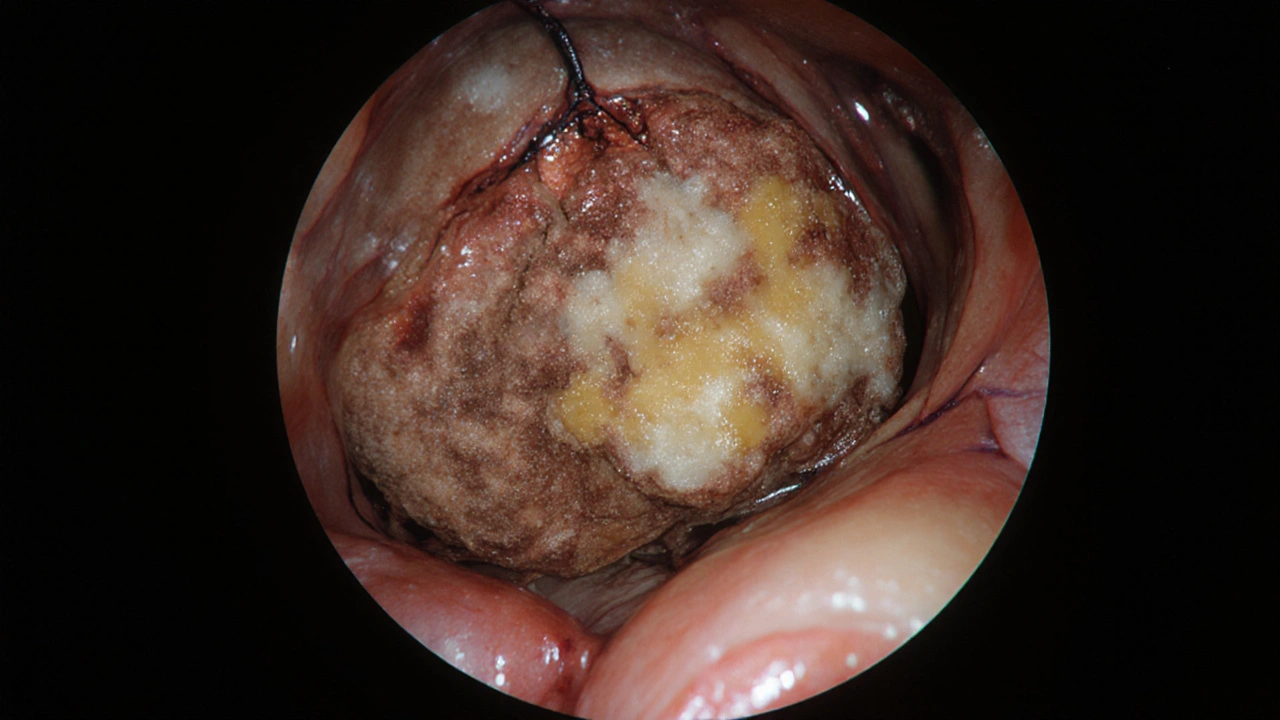

První známka, kterou lékaři často pozorují, je nepravidelný výrůstek. Nejde o malý polyp, který je běžný a často neškodný. Tento výrůstek je tvrdý, nepravidelný, často jako kdyby se kůra stromu zhrbila. Barva je často tmavší - od červenohnědé po šedivou. Někdy se na něm objevují malé krvácení, která vypadají jako červené skvrnky nebo kapky.

Třetí příznak je nepravidelná sliznice. Místo hladkého povrchu se objevují hrbolky, vředy nebo zvětšené cévy. Sliznice může být zčervenalá, oteklá, nebo naopak bledá a zaniklá. Někdy se na povrchu objeví bílé nebo žluté placky - to je známka nekrózy, tedy mrtvých tkání, které nádor zničil.

Karcinom v přímém střevě s hrubou, tmavě červenohnědou povrchovou strukturou a nekrózou.